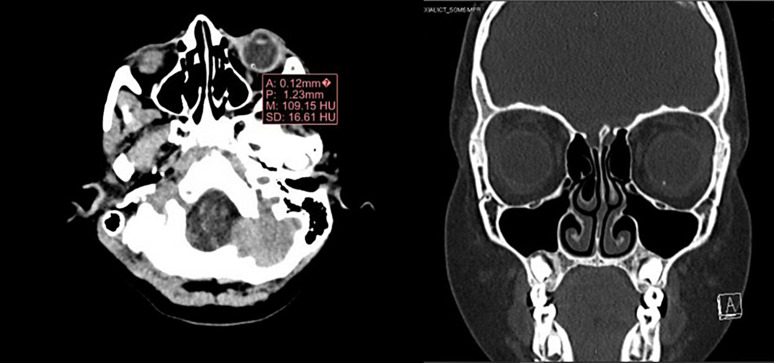

Case presentation: We report a case of a 7-year-old girl with a retained intraocular graphite pencil lead foreign body in the vitreous treated conservatively for more than 5 years without any consequences.

Conclusion: Graphite foreign bodies may be retained in the eye posterior segment without causing any inflammation or damage to the intraocular structures.